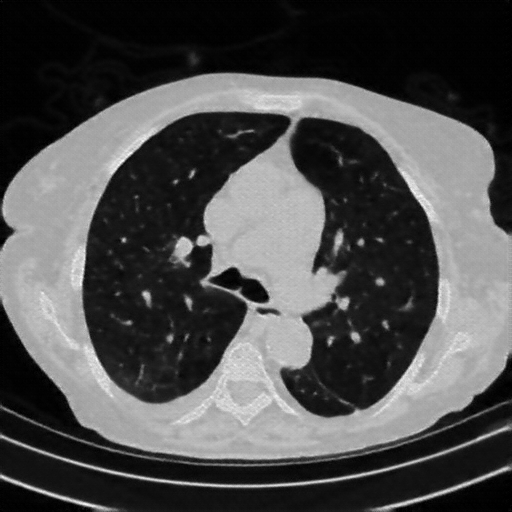

Targeted Slice 70 - Lung Window Analysis (Generated vs Real Venous)

0.583

Lung SSIM

161.5

Lung RMSE

72.4

Lung MAE

Average Lung Window Metrics Across All Slices (153 slices) - Generated vs Real Venous

0.553

Lung SSIM (Avg)

147.1

Lung RMSE (Avg)

69.0

Lung MAE (Avg)

Original VENOUS CT scan

Lung window (WL -600, WW 1500 β†’ Low βˆ’1350, High +150)

Mediastinum window (WL 40, WW 400 β†’ Low βˆ’160, High +240)